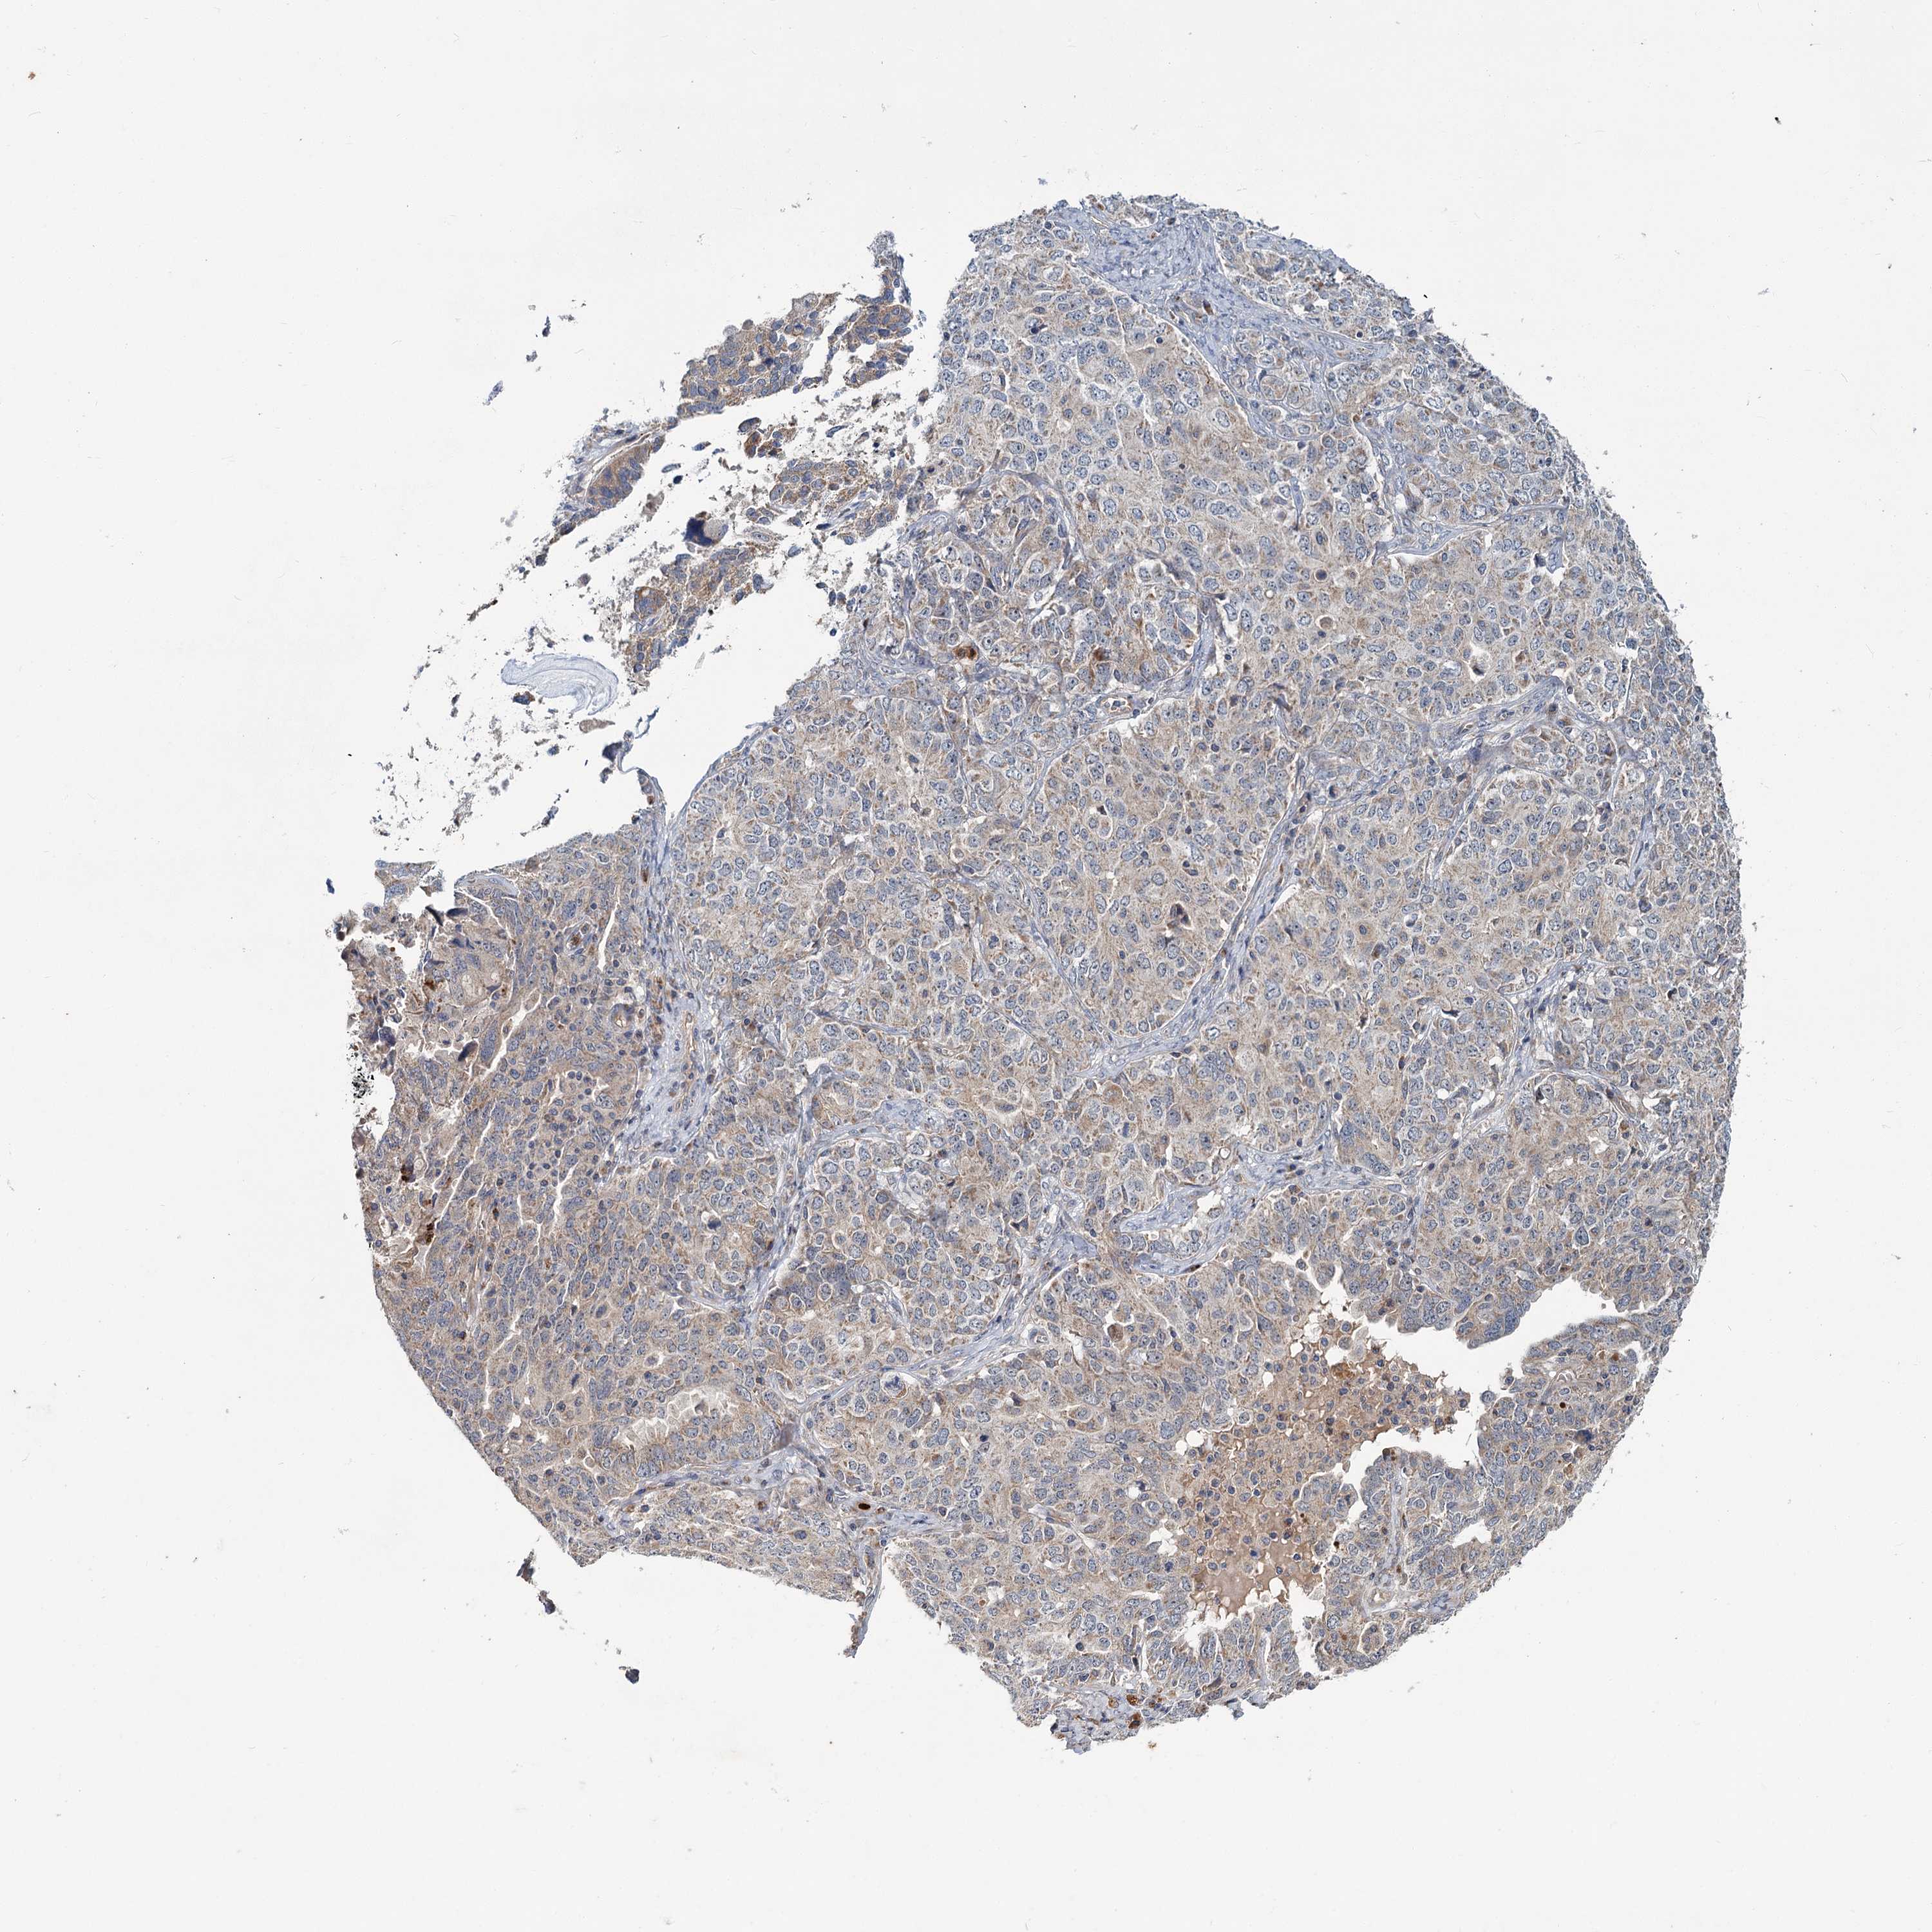

OVARIAN CANCER - Protein expressioni

A mouse-over function shows sample information and annotation data. Click on an image to view it in a full screen mode. Samples can be filtered based on level of antibody staining by selecting one or several of the following categories: high, medium, low and not detected. The assay and annotation is described here.

Note that samples used for immunohistochemistry by the Human Protein Atlas do not correspond to samples in the TCGA dataset.

Antibody stainingi

Antibody staining in the annotated cell types in the current human tissue is reported as not detected, low, medium, or high, based on conventional immunohistochemistry profiling in selected tissues. This score is based on the combination of the staining intensity and fraction of stained cells.

Each image is clickable and will lead to virtual microscopy that enables deeper exploration of all samples and also displays staining intensity scores, fraction scores and subcellular localization as well as patient and tissue information for each sample.

Antibody HPA039015

Antibody HPA039016

Cystadenocarcinoma, serous, NOS